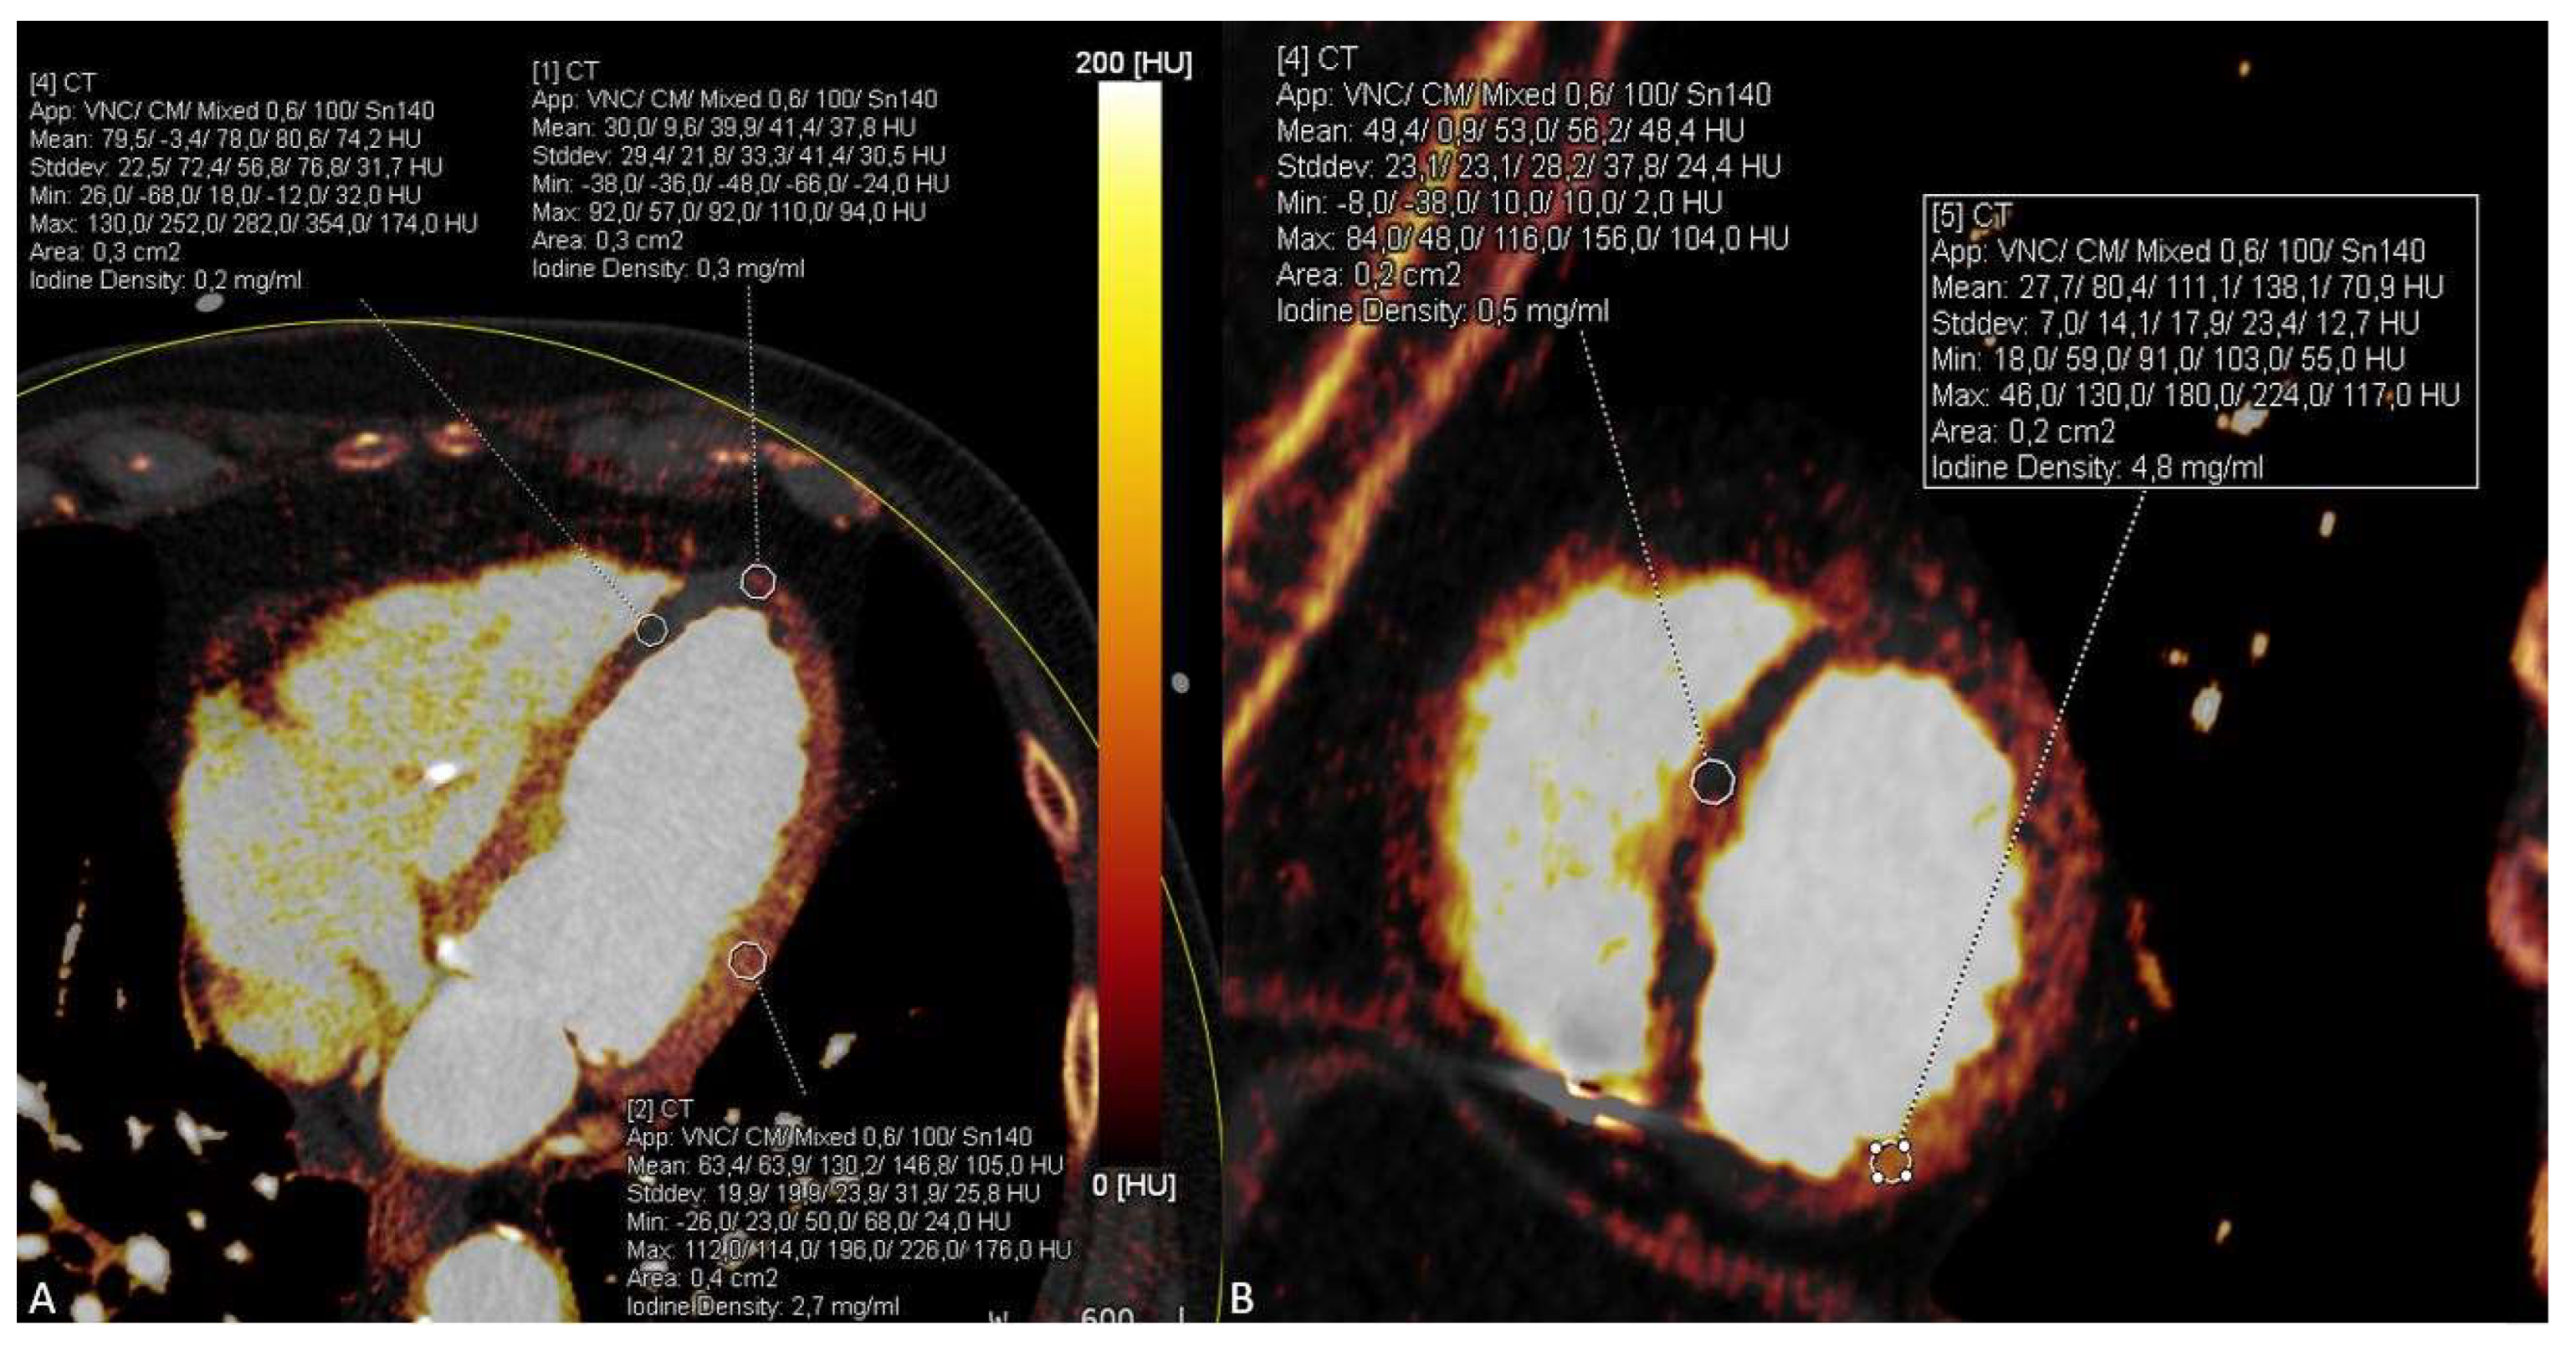

We report the case of a 80-year-old man who presented to our emergency department two days after fall and persistent unclear consciousness. The patient’s medical history included a T-cell lymphoma and a high-grade atrioventricular block treated with a heart pacemaker. Except for chest pain, the patient did not report any medical complaints. Clinically, only a small hemorrhage on the face and ear was noted. Therefore, a cranial CT scan was performed to rule out intracranial hemorrhage. The CT scan showed no evidence of intracranial hemorrhage. Instead, significant reduction in brain volume and a fracture of the nasal bone were detected. After ruling out intracranial hemorrhage, further investigations were performed. The laboratory testing showed elevated levels of the following parameters: C-reactive protein, CK, CK-MB, LDH, Troponin T and D-Dimer. The ECG examination presented acute ST-segment elevation in V1 and V2, suggestive of an anterior wall infarction. The patient was hemodynamically stable and presented improvement in respiration after receiving an anti-infective therapy with Rocephin. Beyond that, a significant decrease in inflammatory parameters was observed. Due to chest pain with syncope and suggestive findings in ECG and laboratory tests with positive D-Dimers and myocardial enzymes, an acute coronary syndrome with syncope was suspected. However, neither an acute pulmonary artery embolism nor an aortic dissection could completely be excluded as differential diagnoses in this constellation. Thus, a triple-rule-out (TRO) DECT scan of the chest was performed. The ECG-gated CT examination was performed on a third-generation, dual-source computed tomography (Somatom® Force, Siemens Healthineers, Forchheim, Germany) consisting of a triple-rule-out scan protocol. According to patient weight, 100 mL of 350 mg iodine/mL (Imeron) was injected into a peripheral vein at a rate of 4 mL/s through a double-piston power injection. After an unenhanced scanning, which is an essential part of our standard protocol, an early contrast-enhanced phase was acquired using test bolus scanning in the descending aorta. The late enhancement scan was obtained 7 min after injection of the contrast medium for myocardial assessment. The total radiation dose was 547 mGycm. CT-scan parameters were as follows: tube A had a voltage of 100 kV and tube current of 165 reference mAs and tube B had a voltage of 140 kV and a tube current of 140 reference mAs. Care Dose4D was applied. All contrast-enhanced CT image series were performed in DECT mode and reconstructed using a medium-soft reconstruction kernel (Qr40f) with a 0.5 mm section collimation in a 0.5 mm increment in the axial, coronal and sagittal planes. In addition, a weighted mix of DECT reconstructions from the 100 kV and 140 kV image data (with a tin filter) were generated to simulate conventional 120 kV images (simulated 120 kV) in all planes. DECT image series were post-processed on a DECT workstation (syngo.via, version VB10B, Siemens Healthineers) to generate virtual monoenergetic images at 55 keV and iodine maps using default settings. While the conventional CT series demonstrated multiple soft and calcified plaques in the left anterior descending (LAD) artery with questionable presence of contrast media in the distal course (Figure 1), the VMI series at 55 keV clearly showed a total LAD occlusion (Figure 2).

Furthermore, the DECT-based iodine maps demonstrated significant hypoperfusion of the anterior wall and anterior septum suggestive for an acute anterior wall infarction, which was missed on conventional CT series (Figure 3). Pulmonary artery embolism and aortic dissection were excluded.

Figure 2. In comparison with the conventional arterial CT image (A), the complete lack of iodine in the distal course of the LAD can be visualized by application of dual-energy CT-based virtual monoenergetic images at 55 keV (B, arrow) and corresponding iodine maps (C, arrowhead).